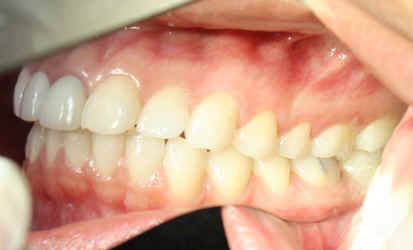

23 year-old female, "I want braces"

Dental history: #9 fracture at age of 8; #9,10 crowns (joined) 2 years ago; #9 has chronic apical infection, #19 extracted due to caries at age of 15

#18 mesiolingual tilt, #19 traditional implant and extract #17; once #19 implant is osteointegrated, it is to be used as an anchorage to upright #18, elastics between #15 buccal hook and 18 lingual button to correct linguoversion of #18